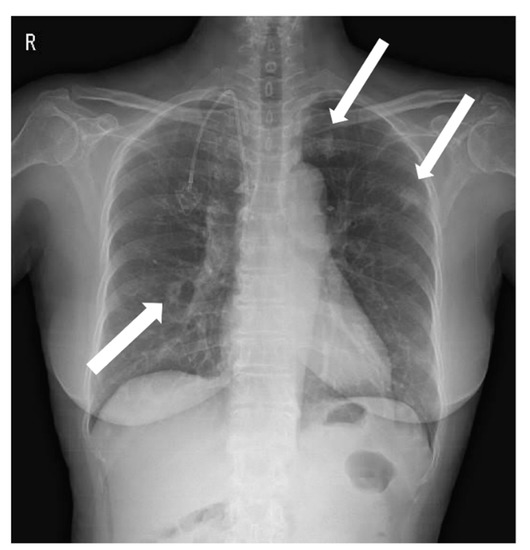

Figure 1. A chest X-ray was performed at admission, showing scattered nodular opacities in the left lung upper lobe and right lung lower lobe, which indicated a central area of excavation (arrows). 18F-fluorodeoxyglucose positron emission tomography/computed tomography (18F-FDG PET/CT) has increasingly been used to manage cancers and infections [1,2,3]. Since FDG uptake is directly representative of glucose metabolism, it can increase in inflammatory cells as well as tumor cells. Long-term indwelling central venous catheters are necessary for treating cancer patients due to chemotherapy. They depend on their central venous catheters daily, which could predispose a significant risk of complications such as catheter-related bloodstream infection (CRBSI) [4,5,6]. CRBSI can be complicated by metastatic infectious foci associated with a high morbidity and mortality rate, which should require prolonged systemic antimicrobial treatment [7]. The significant complication of CRBSI is septic thrombosis, with a prevalence of 15~24% [8,9]. The clinical diagnosis of septic foci is critical but may be difficult to establish due to the challenge of determining between sterile catheter-related thrombosis and actual septic thrombosis. Additionally, symptoms are often non-specific, and there is a lack of sensitivity to conventional diagnostic imaging techniques. Only a few studies investigated that 18F-FDG PET/CT can find the infectious foci, demonstrating it as an accurate imaging modality for metastatic foci [10,11,12]. Here, we would like to report a female patient with a Staphylococcus aureus-implantable venous access catheter infection in which 18F-FDG PET/CT determined unsuspected septic pulmonary emboli. A 71-year-old female patient with known ovarian cancer visited our hospital to receive the 4th adjuvant chemotherapy. She was treated with total abdominal hysterectomy, bilateral salpingo-oophrectomy and omentectomy 6 months ago. She also had a history of central venous catheterization by the right internal jugular vein approach, terminating at the junction of the superior vena cava and right atrium. The adjuvant chemotherapy was already performed three times as the regimen of Paclitaxel plus Carboplatine after surgery. At admission, she presented no clinical symptoms such as fever, cough, sputum, dyspnea, or chest pain. However, the chest X-ray showed scattered nodular opacities in the left lung upper lobe and right lung lower lobe, suspicious of metastatic nodules (Figure 1). Her blood test showed unexplained leukocytosis (12.58 × 103/μL), elevated D-dimer (9.46 mg/L), and a tumor marker such as CA-125 (41.89 U/mL). 18F-FDG PET/CT was performed 2 days after admission, observing abnormal FDG uptake in the chemo-port catheter, right pectoralis muscle, and 1st costochondral junction (Figure 2a–d). PET/CT also revealed hypermetabolic nodules scattered throughout both lungs, consistent with septic embolism (Figure 2e). In the evening of the day of the PET/CT examination, the patient presented swelling, redness, and some discomfort at the catheter insertion site. The catheter was removed the next day, isolating methicillin-sensitive Staphylococcus aureus from the catheter tip and peripheral vein. A transthoracic echocardiogram and fundus examination, which were performed to evaluate possible metastatic infections such as infective endocarditis or endophthalmitis, were reported as normal. She was treated with intravenous cefazolin for 4 weeks followed by oral linezolid for 1 week, recovering uneventfully without relapse. She was also treated with rivaroxaban 15 mg for 3 weeks and was diagnosed with pulmonary thromboembolism. After 2 months, a follow-up chest CT showed that the pre-existing multiple nodules in both lungs had disappeared (Figure 3).